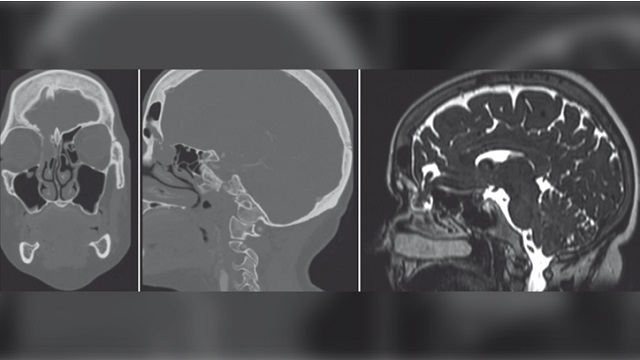

2020 yılı Ekim ayında JAMA (The Journal of the American Medical Association – Amerikan Medikal Birliği Dergisi) Otolaryngology – Head & Neck Surgery dergisinde yayınlanan bir rapora göre; burun çubuğu testi esnasında beyin zarı delinen bir kadında, beyin omurilik sıvısı sızıntısı görülmüştür. Birleşik Devletler’de başka bir kadında da geçtiğimiz günlerde benzer bir vakaya rastlanmıştır. Burun çubuğu kullanımını değerlendiren ve görüşlerini JAMA Otolaryngology – Head & Neck Surgery dergisinde paylaşan araştırmacılar, özellikle uygun kullanılmayan burun çubukları nedeniyle, rutin olarak test yaptıran milyonlarca insanın risk altında olduğu uyarısında bulunmuşlardır.

Peki, okullarda burun çubuklarını PCR testleri için kim kullanmaktadır? Ne yazık ki okul çocuklarının kendileri bu testleri uygulamaktadır. Ümit eldim ki çocuklar hata yaptıklarında fazla derine gitmemiş olsunlar. Hiç kimseye anlatılmamış gibi görünen bir ayrıntı ise aşağıdaki şekilde görülen etmoid kemiğinin kalbur şeklindeki delikli bölümü olan süngerimsi duvarın oldukça hassas, yumuşak ve bal peteği veya elek şeklinde küçük delikli ince ve dar bir yapı olduğudur. Endoskopik transnazal kafatası temelli operasyonlar için mükemmel bir giriş yeri olmasının nedeni tam da budur. Ancak, süzüntü testi için burun çubuğu kullanmakta yeteri kadar usta olmayan birinin, pamuklu çubuğu asla beyne kadar itmeyeceğini ileri sürmenin saçma bir düşünce olduğu da açıkça görülmektedir.

Doktorlar kadının burnu içinde bir kitle tespit etmişlerdir ve bu kitlenin burun çubuğu uygulaması esnasında oluşarak beyin omurilik sıvısının akıntısına neden olduğuna inanmaktadırlar. Kaynak: JAMA Otolaryngology/University of Iowa Hospitals and Clinics.